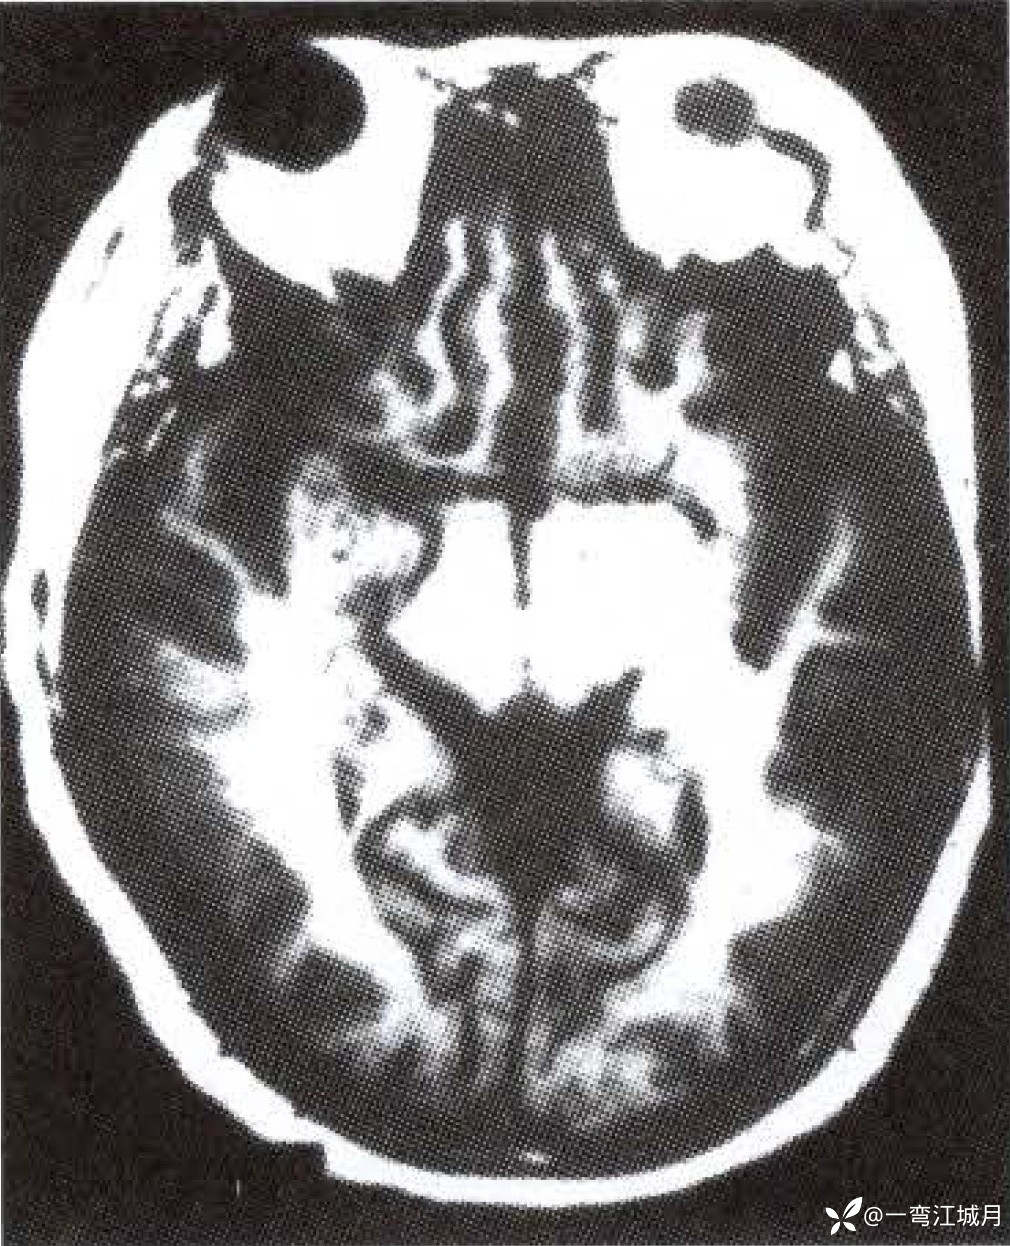

影像学征象:MRI T1WI(图1-A)示双侧大脑半球脑底内侧很多纤细、不规则的具有流空效应的点条状异常血管网。T2WI(图1-B)示脑底部、 Willis 环旁及侧裂池内许多迂曲的流空血管影;矢状面T2WI(图1- C , D )示脑底向上至大脑半球许多断续呈放射状分布的流空异常血管网及脑顶部许多小片状高信号梗死灶。右侧颈内动脉 DSA 示额顶区扇形广泛分布异常血管网。